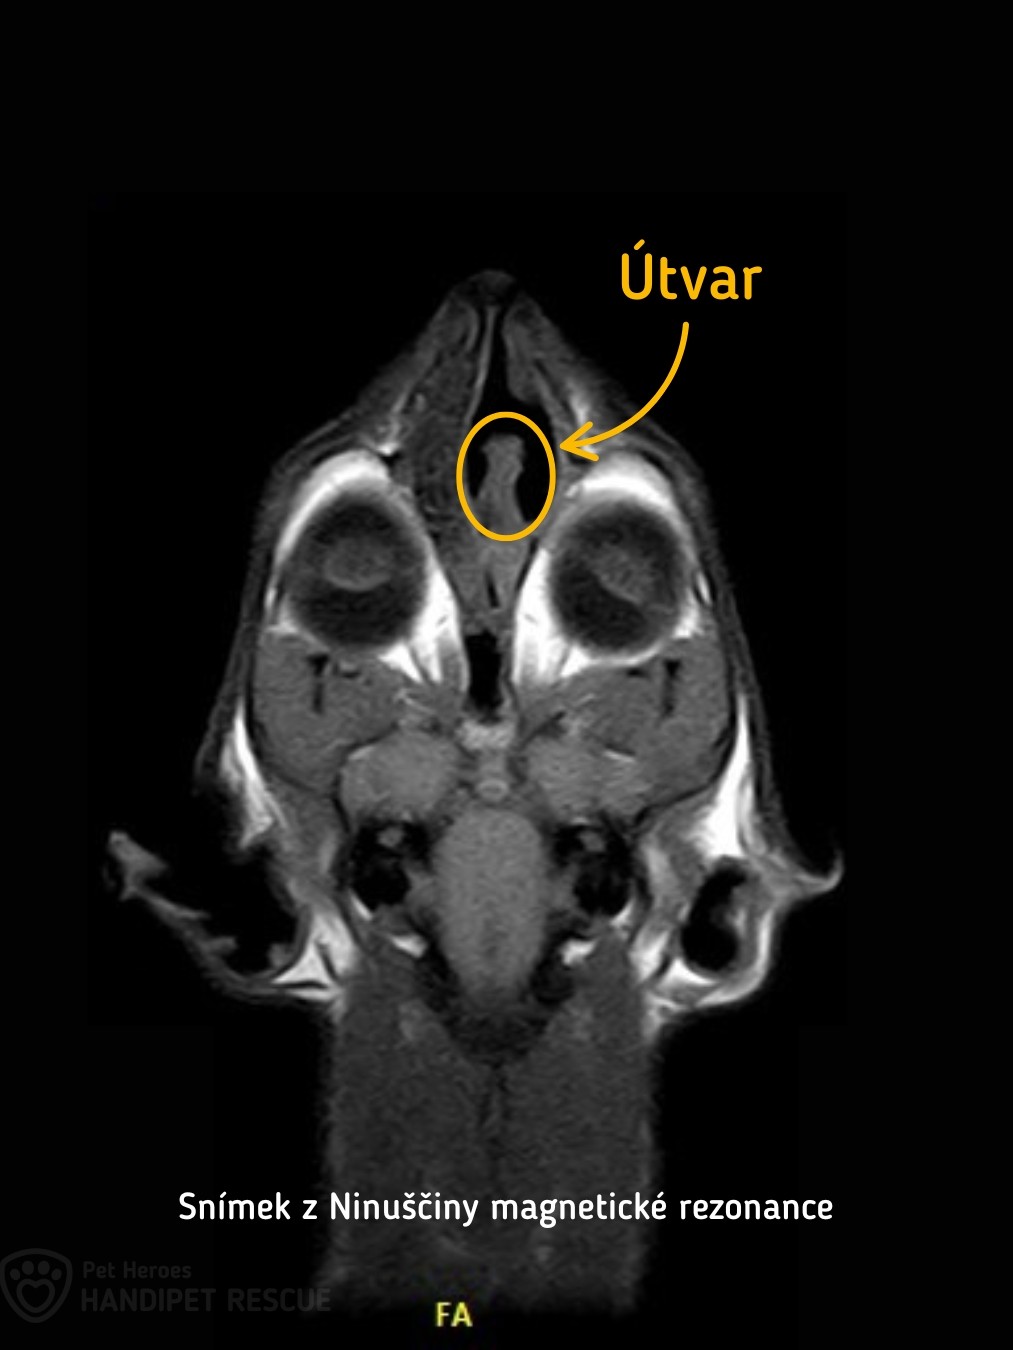

To ale bohužel nebylo všechno, protože se ještě navíc ukázalo, že má Ninuška hluboko v nosu podezřelý útvar.

Útvar v nose jsme konzultovali se specialisty na veterinární onkologii. Podle nich jde s největší pravděpodobností o nádor. S úplnou jistotou to ale potvrdit nedokázali, protože útvar byl tak hluboko, že ho nedokázali odoperovat ani bezpečně odebrat vzorek. Pro jistotu jsme Ninu vzali ještě na ultrazvuk plic a SONO bříška, abychom se ujistili, že nemá nádory i někde jinde – naštěstí jsme ale nic dalšího nenašli.

Nina byla na magnetické rezonanci

Po dvou letech onkologické léčby bylo načase nádor zkontrolovat. Léky, které Nina bere, totiž mohou přispět ke zmenšení útvaru a kdyby se smrskl úplně na minimum, mohli bychom podle paní doktorky dokonce zkusit léčbu ukončit. Bohužel podle snímků z magnetické rezonance byl ale útvar stále zhruba stejně velký jako na začátku.